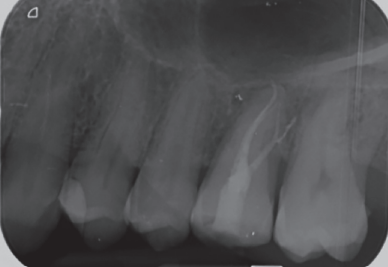

There were no medical-surgical antecedents of interest in his medical history, without known drug allergies or unhealthy habits. No relevant data was found on the extra oral examination. In the intraoral examination, non-restorable teeth were seen in the 2.6 and 4.6 position and the presence of retained lower third molars. (Figures 1 and 2).

In the radiograph examination, through a panoramic radiograph, both lower third molars were seen retained in horizontal position (Figure 3), and apical radiolucent images in positions of 2.6 and 4.6. The cone beam scan evaluated the root morphology of the left upper third molar and the size of the apical radiolucent lesion of the left upper first molar (Figure 4), necessary data to assess the degree of adaptation of the donor tooth in the recipient bed.

associated with the root remains of 2.6 and the conical root of 2.8 are seen.